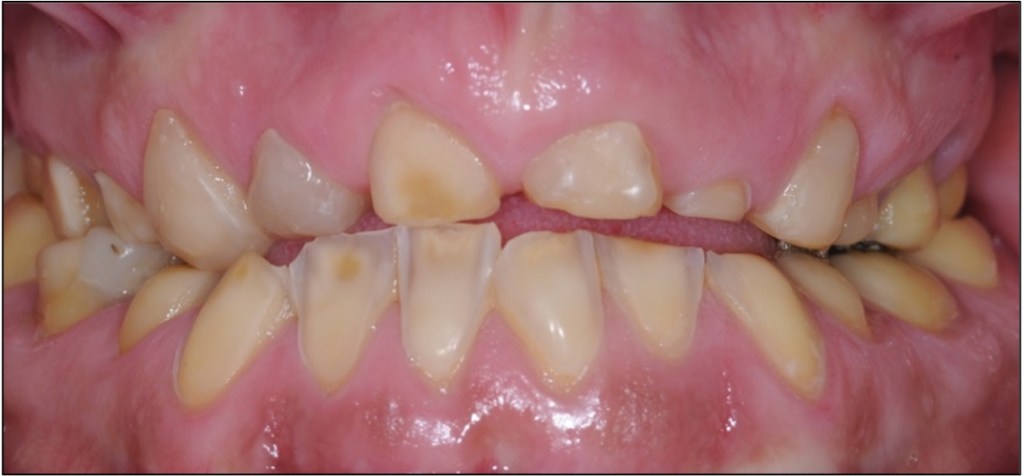

Direct composite is often used to treat toothwear. It is a minimally invasive method that does not damage the underlying tooth structure. It can chip, stain and fail. However, replacement and repair is more straightforward. This case was treated with direct composite alone.